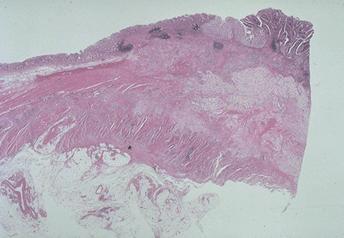

질환(병리주체)의 분류 악성 상피성종양/인환세포암

부위(장기별) 대장/직장

검사방법 마이크로

종양의 육안분류 3형(궤양침윤형)/

종양의 최대경(밀리미터) 35~40

종양의 심달도 s(a)